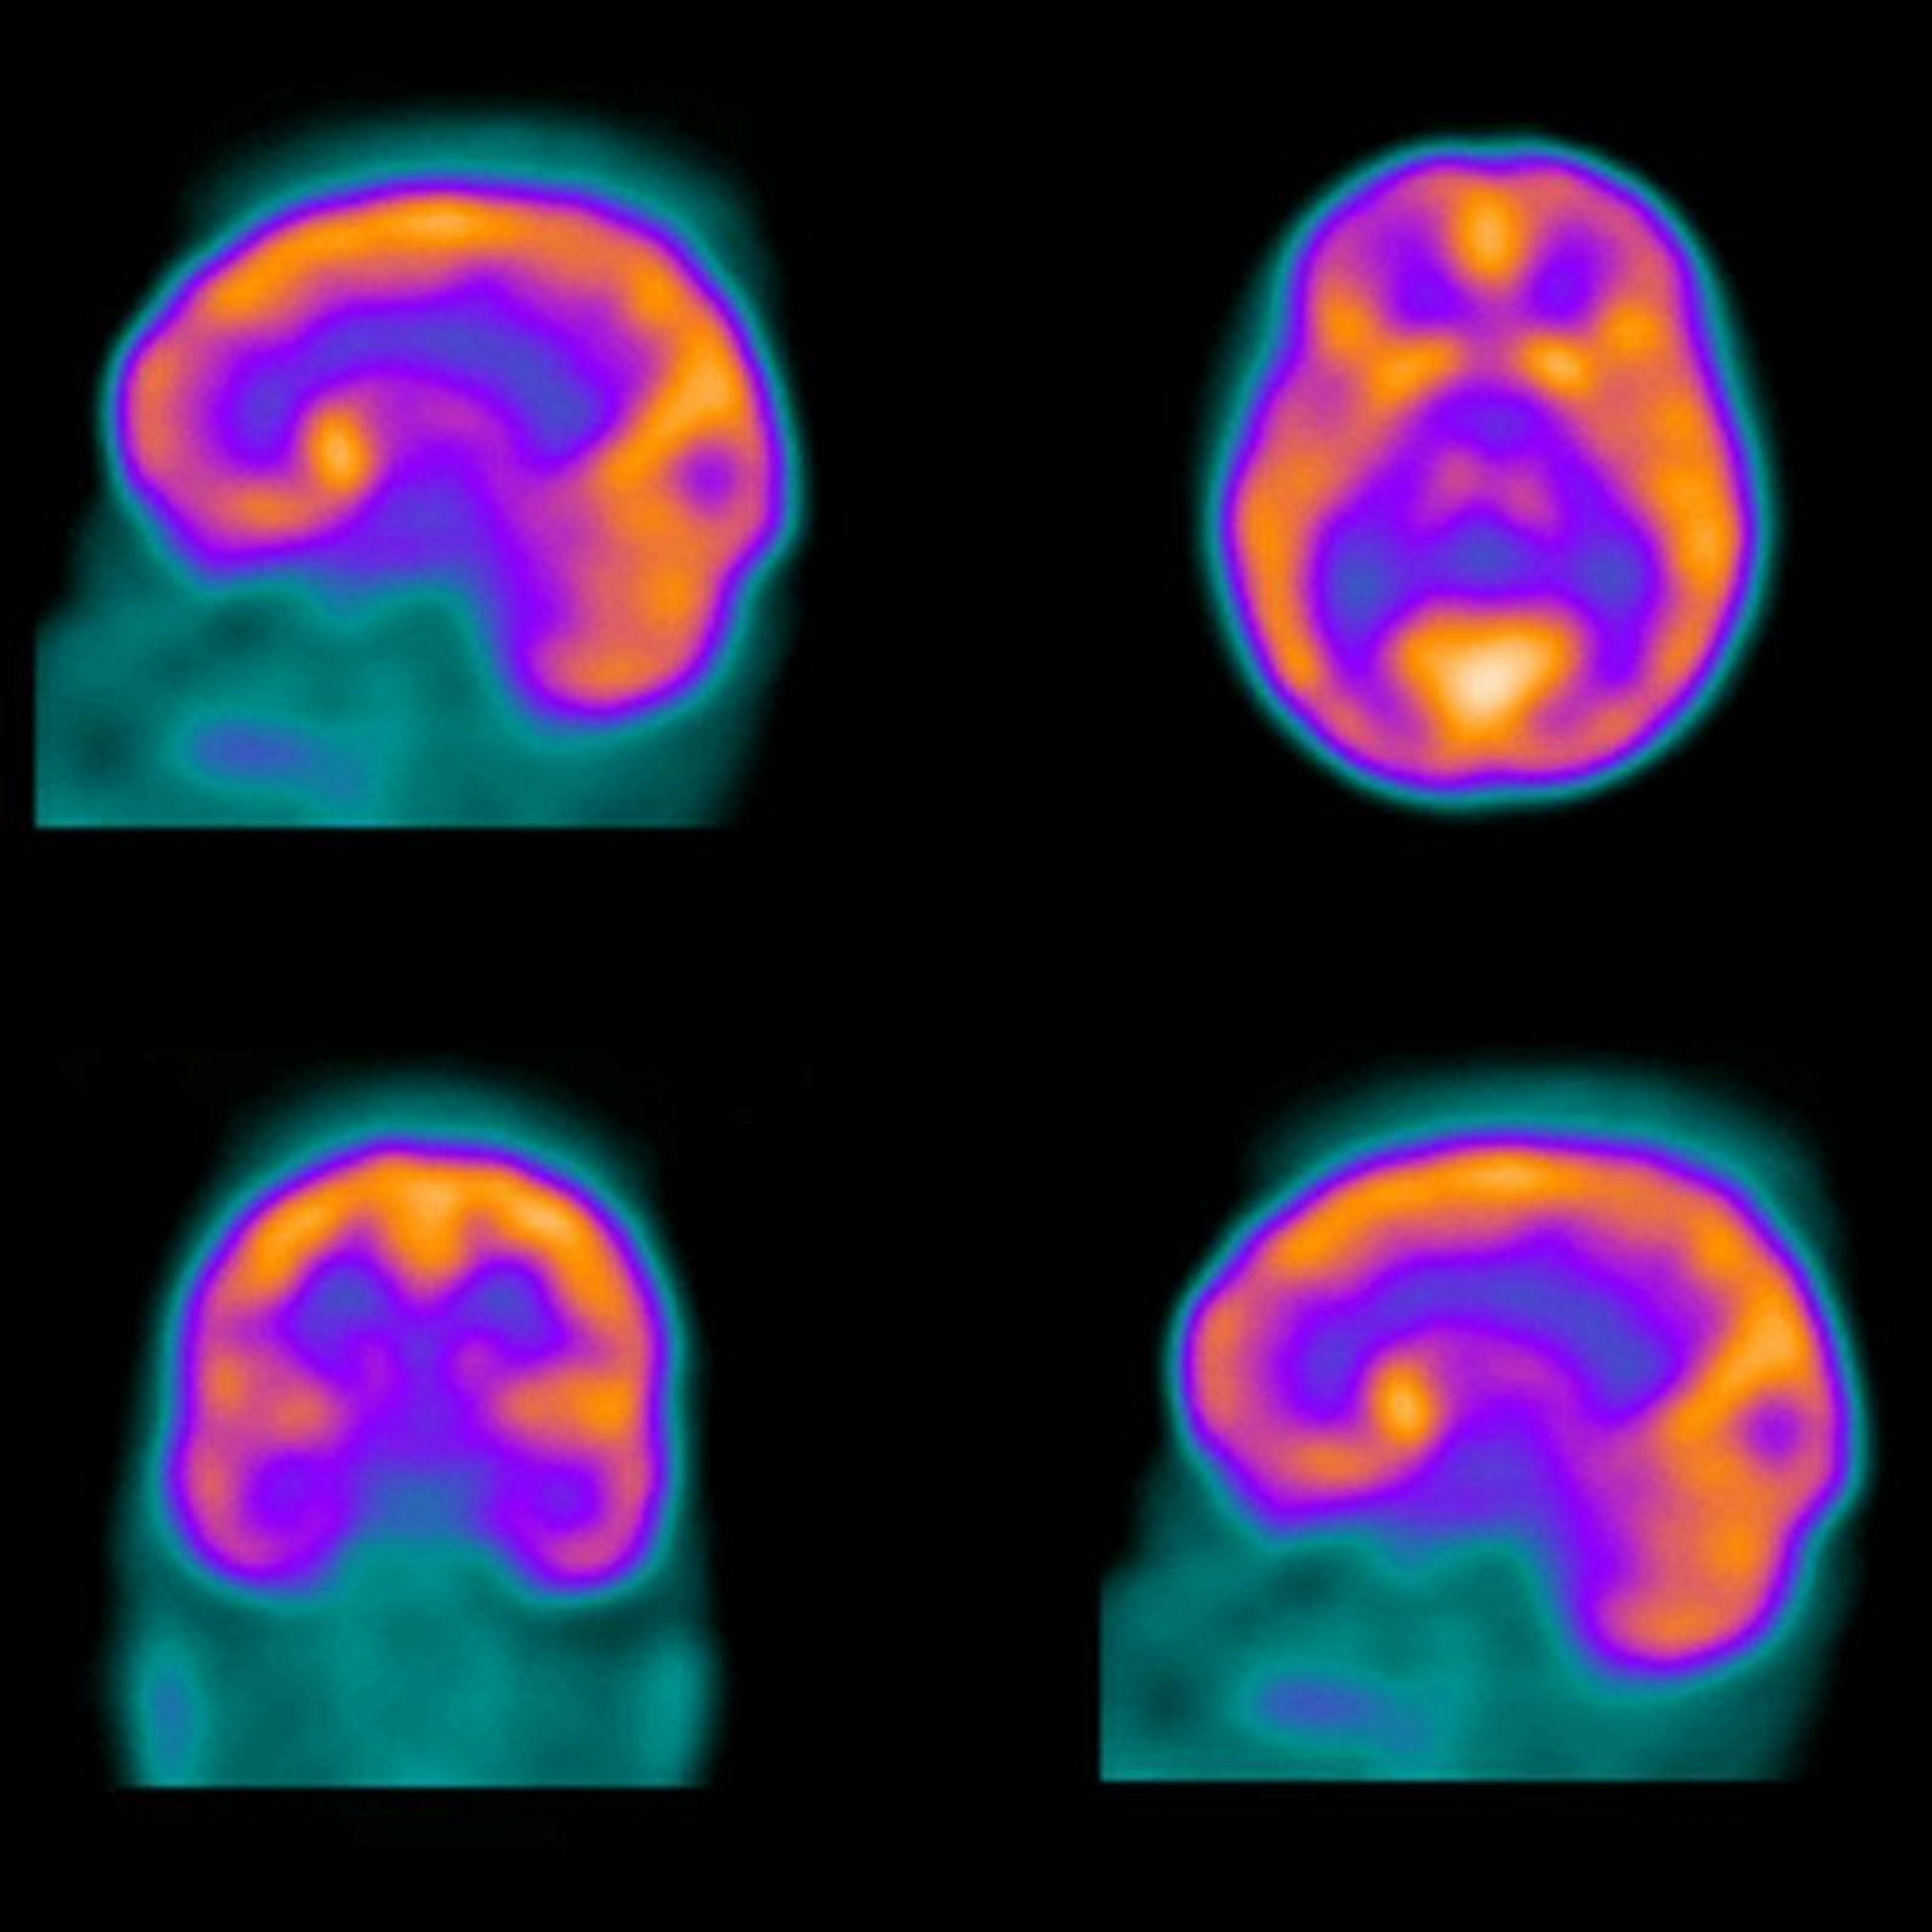

Diagnosing brain disorders can often be a challenge for doctors, as some psychological diseases have overlapping symptoms. These include memory loss in patients with depression and suppressed mood in people suffering from dementia. But neuroimaging and machine learning can help improve diagnosis. In fact, radiologist Cyrus Raji of the University of California, San Francisco, led a study to prove just that.

“Each individual had a perfusion neuroimaging, where there is a nuclear tracer injected into them and that allowed the mapping of the blood flow in the brain. And that allow us to quantify blood flow in 128 regions of the brain and use machine learning analysis to separate who had depression or cognitive disorders or both."